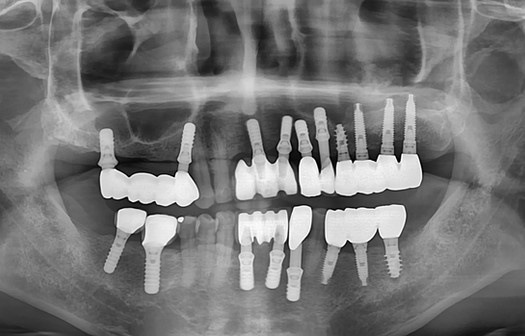

Pre-operative radiograph shows peri-implant bone loss around the #37

Post operative radiograph

Intraoral photograph and periapical radiograph show the final prosthesis seated with proper fit and stability using the CL-Link.

At 3 months, the prosthesis remains functional and peri-implant bone levels are well-maintained.